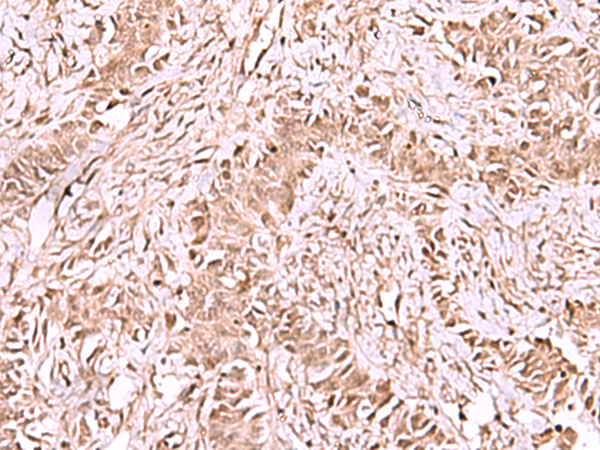

IHC positive control: |

Human cervical cancer and Human ovarian cancer |

IHC Recommend dilution: |

50-300 |